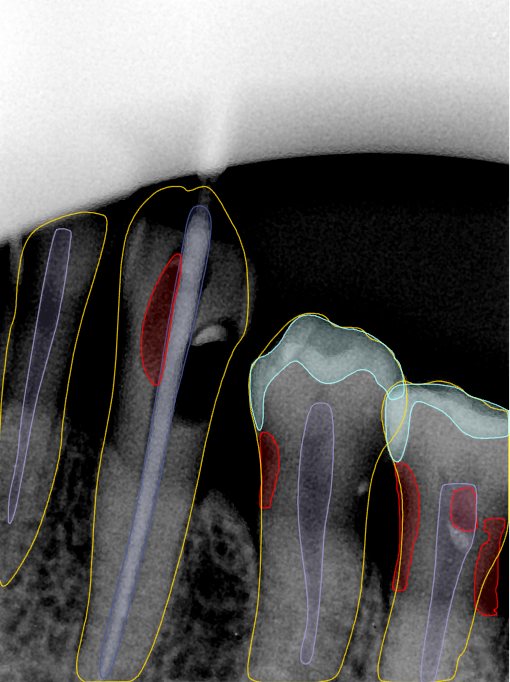

CR/DR 牙齿分割阶段记录

当前进展

- 完成了 CR/DR 牙齿相关分割训练

- 当前结果已经达到阶段预期,但仍有细节问题需要继续处理

相关测试

遇到的问题

- 训练过程中出现过 mask 下移问题

- 部分结果会出现 box 填充异常

- mask 边缘仍然有比较明显的锯齿感

第二版算法问题测试

| 第一版 | 第二版 | 是否解决 | |

|---|---|---|---|

![]() | ![]() ![]() 边角识别有问题 龋齿识别不全 牙髓识别不全 | ![]() | 解决 |

![]() | ![]() 边角识别有问题 识别信息有误 自查(牙冠识别不全) | ![]() | 解决 |

![]() | ![]() ![]() 边角识别有误 大范围填充识别遗漏 | ![]() | 解决 |

![]() | ![]() 识别信息不全 | ![]() | 解决 |

![]() | ![]() ![]() 边角问题 牙胶识别不全 牙冠识别不全 | ![]() | 解决 |

![]() 换图片 | ![]() | ![]() 牙冠部分稍微白了一些就识别成小范围修补,部分判断异常 | 部分解决,修复类略敏感,牙冠部分稍微白了一些就识别成小范围修补,部分判断异常。 |

![]() | ![]() ![]() 牙冠识别不全 牙髓不全 根尖炎龋齿识别有误 | ![]() | 解决 |

![]() | ![]() | ![]() | 解决 |

![]() 换图片 | ![]() | ![]() | 解决 |

![]() | ![]() 牙冠识别有误 | ![]() | 解决 |

![]() 换图片 | ![]() ![]() 边角识别有误 | ![]() 修复类敏感 | 部分解决,图像过白,导致修复类判断异常。 |

![]() 换图片 | ![]() 牙冠识别不全 | ![]() 修复类敏感 | 部分解决,图像过白,导致修复类判断异常 |

结论:修复类出现了不鲁棒的情况,后续需要加入轮廓的扩充数据进行增强。